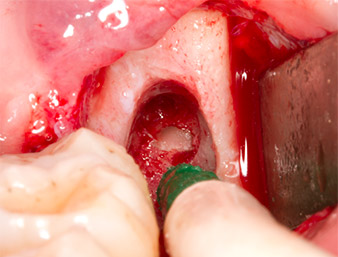

The tissue above the root remnant was not completely ossified and consisted for the most part of granulation tissue modified by inflammation (Fig. 4).

To obtain autogenous material for subsequent wound treatment, healthy bone chips were harvested from the surroundings of the root remnant with a piezo surgical instrument (Piezomed B5) (Fig. 5).